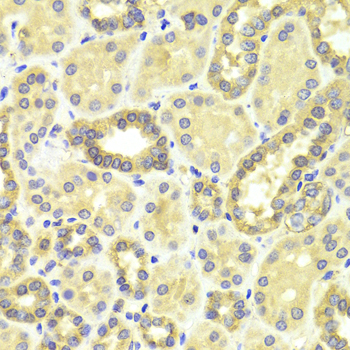

• A0253: image 2

Immunohistochemistry of paraffin-embedded human kidney using MAP2K2 antibody at dilution of 1:100 (x400 lens).